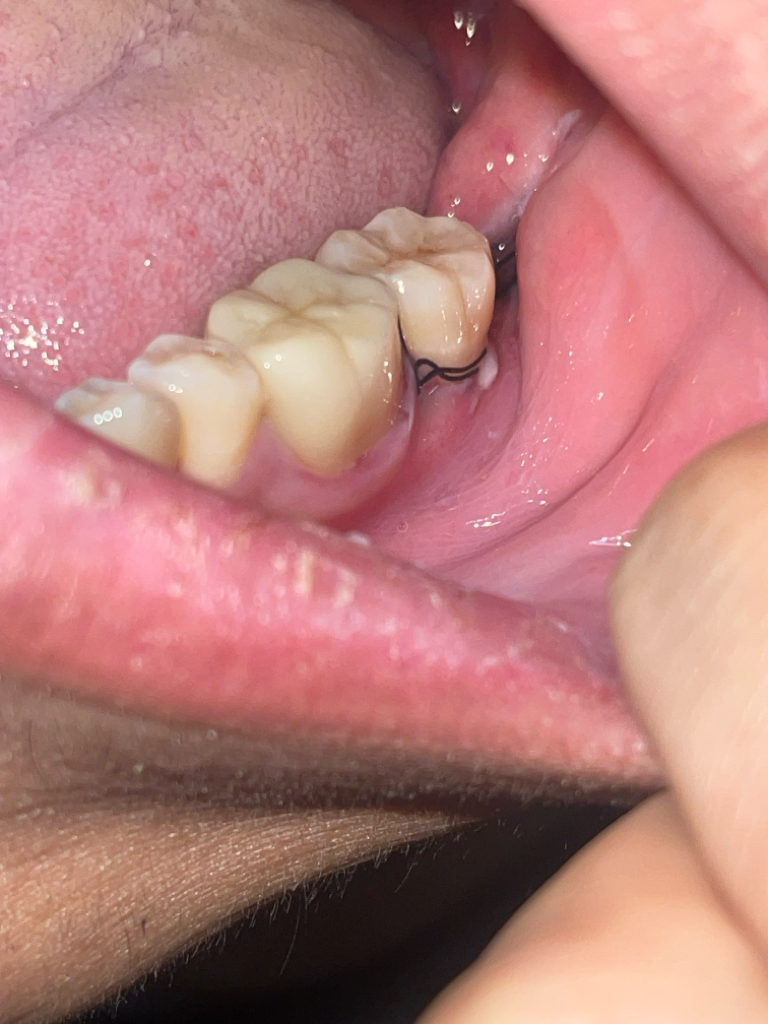

매복사랑니 발치후 혈병이 빠지면 병원을 가봐야할까요?(사진첨부)

안녕하세요 어제 11시경 사랑니 발치후 24시간 정도가 지났습니다 통증은 마취풀렸을때 이후 큰통증은 없지만 혈병자리를 확인하다가 이게 빠진건지 어떤상태인건지 모르겠어서 질뭉드립니다. 안에 실밥이 보이는데 혈병이 떨어져서 실밥이 보이는걸까요?

• 2번 째 사진

현재 사진상 문제가 되어 보이지 않으며 잘 아물고 있는 것으로 보이기에 치과에 방문하지 않으셔도 됩니다. 해당부위에 염증이 덧나지 않게 헥사메딘 가글액으로 가글을 하고, 흡연 및 음주는 7일간은 피하길 권합니다.

1. 봉합실은 원래 보이는 것이 맞습니다.

2. 혈병은 1~2일차에 잇몸 상피세포로 바뀌므로 혈병이 탈락하거나 그런 것이 아니라 자연스러운 치유 과정일 수 있습니다.

3. 발치 후 주의사항 잘 지키면 치유에 아직까지는 큰 문제는 없을 것 같습니다.